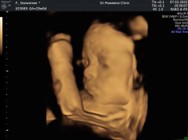

รูปนี้น้อง1724ค่ะ 30w ซาวด์แบบนี้ซาว์มา1300ค่ะ

บ้านนี้21เมษาคะ ซาวด์ตอน25w น้องเป็นเด็กผญ.คะ

ซาวตอน27w ค่ะ กำหนดคลอด18 เมษาค่ะ

ซาวด์ตอน29weeksจ้า🥰